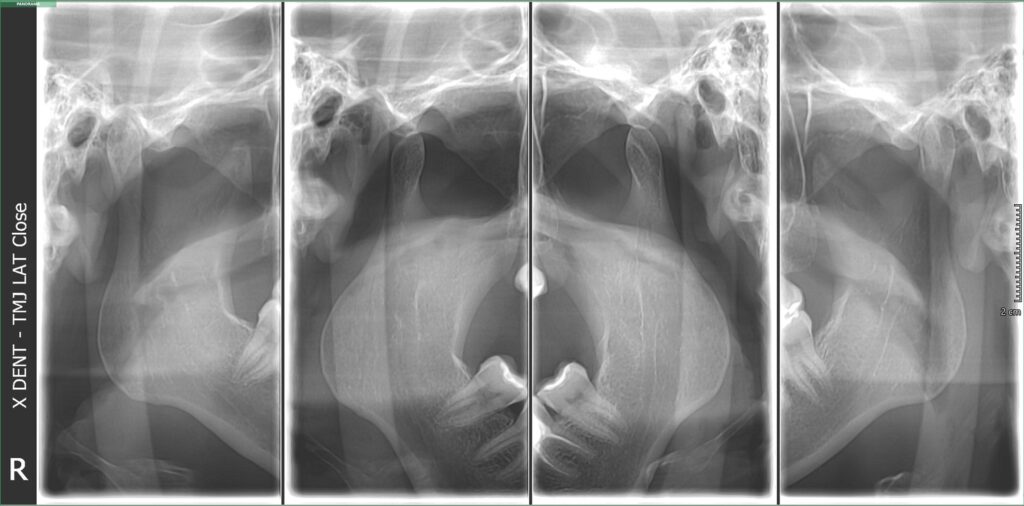

Snimanje temporomandibularnih zglobova

Snimanje TM zglobova predstavlja ključni dijagnostički korak za utvrđivanje stanja i eventualnih poremećaja temporomandibularnih zglobova. Snimak omogućava stomatologu ili maksilofacijalnom hirurgu da precizno sagleda anatomiju zgloba, identifikuje upalne procese, degenerativne promene, dislokaciju diska i druge abnormalnosti.

Snimanje u zatvorenom i otvorenom položaju vilice – kako bi se uporedili pokreti zgloba

Analizu snimka – specijalista procenjuje stanje kostiju, diska i eventualne promene